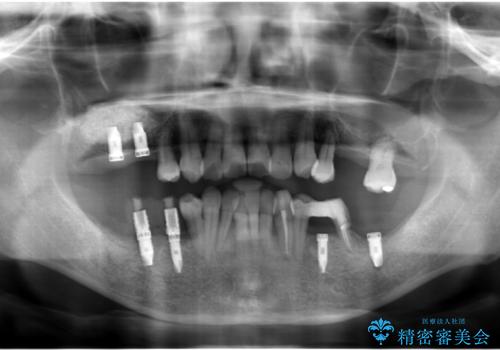

インプラント治療を併用した全顎歯周病治療

全体的に重度の歯周病が認められ、抜歯が必要な部位はインプラント治療を、残すことのできる歯には再生治療を含めた歯周病治療を行い全体的な治療を進めてきます。

全顎的治療について

工程も多く、治療期間も長くなりがちですが、しっかりと通っていただいたおかげで安定した噛み合わせで食事を楽しむことができるようになりました。

メンテナンスも定期的に行うことで安定した状態を保っています。